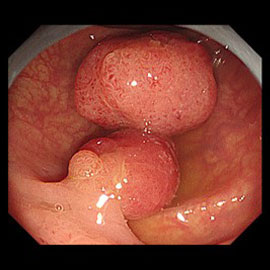

大腸 EMR

2、ポリペクトミー、内視鏡的粘膜切除術(EMR)

従来の高周波電流を用いて治療を行う治療法です。コールドポリペクトミーでは治療ができない、より大きなポリープ(約20mm以下の腺腫、又は早期癌)の治療法です。

ポリペクトミーとは茎のある病変に対し、茎にワイヤー(スネア)をかけ絞扼し高周波電流を用いて切除する方法です。EMRとは茎のない病変の下の粘膜下層へ生理食塩水などを注入し、病変を浮き上がらせてワイヤー(スネア)をかけ絞扼し高周波電流を用いて切除します。